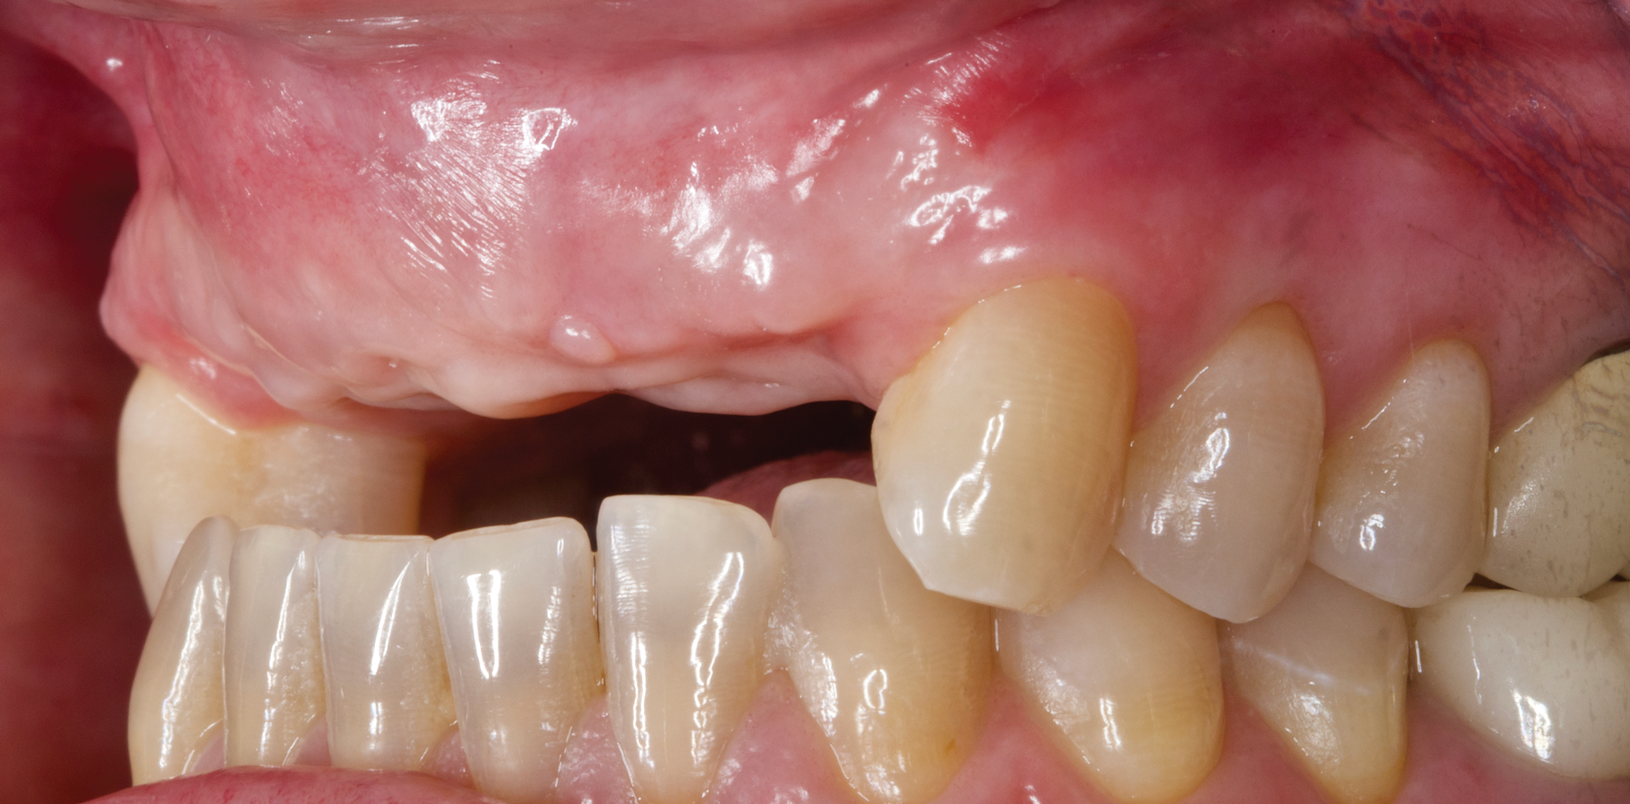

A male patient presented with classic ectodermal dysplasia, a congenital anomaly caused by a single abnormal gene or pair of abnormal genes.11 The typical malformation of the alveolar ridge, bone deficiency, and absence of tooth buds were evident (Figure 7).

Fig 7. Case 2, initial situation at presentation.

Figure 7